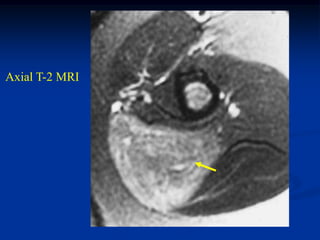

Case #1185

59 year female with

intramuscular lipoma

anterior proximal thigh

Coronal T-1 MRI

Axial T-2 MRI

at lower level

Fat subtraction MRI

showing signal void

in lipoma